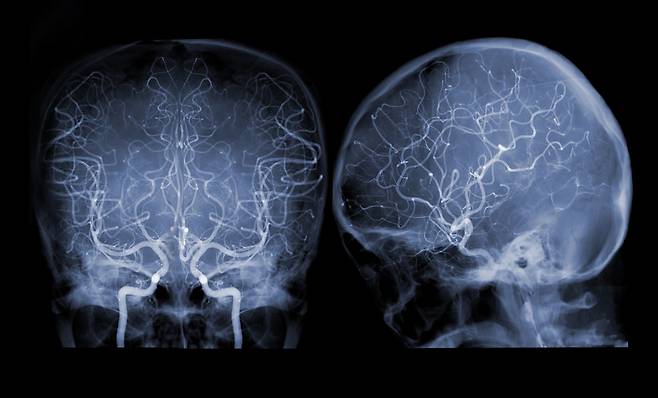

방사선은 우리 몸을 투과하면서 세포 내에서 전리현상을 일으킨다. 전리현상으로 세포 분자에서 전자가 떨어져나가면 세포의 생존에 필수적인 DNA 또는 세포막에 화학적 변성이 발생한다. 암세포도 예외는 아니기 때문에 방사선은 보통 암 치료에 활용된다. 암 치료에 쓰이는 방사선량을 1/20으로 줄인 게 저선량 방사선이다. 주로 폐 CT 등 진단에 활용되는데 퇴행성 관절질환 등에 항염증 효과가 보고된 이후 알츠하이머 치매 증상 완화에도 효과가 있는지 연구가 진행 중이다.

중간 결과에 따르면 모든 인지기능 검사에서 대조군(방사선 치료를 시행하지 않은 군)보다 저선량 방사선 치료를 받은 환자들에게서 유의미한 인지 기능 개선이 나타났다. 또 저선량 방사선 치료를 받은 환자들의 50%는 MRI 상 뇌 용적 변화가 없는 것으로 나타났다.